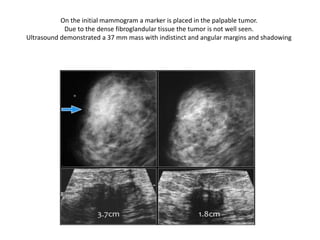

On the initial mammogram a marker is placed in the palpable tumor.

Due to the dense fibroglandular tissue the tumor is not well seen.

Ultrasound demonstrated a 37 mm mass with indistinct and angular margins and shadowing